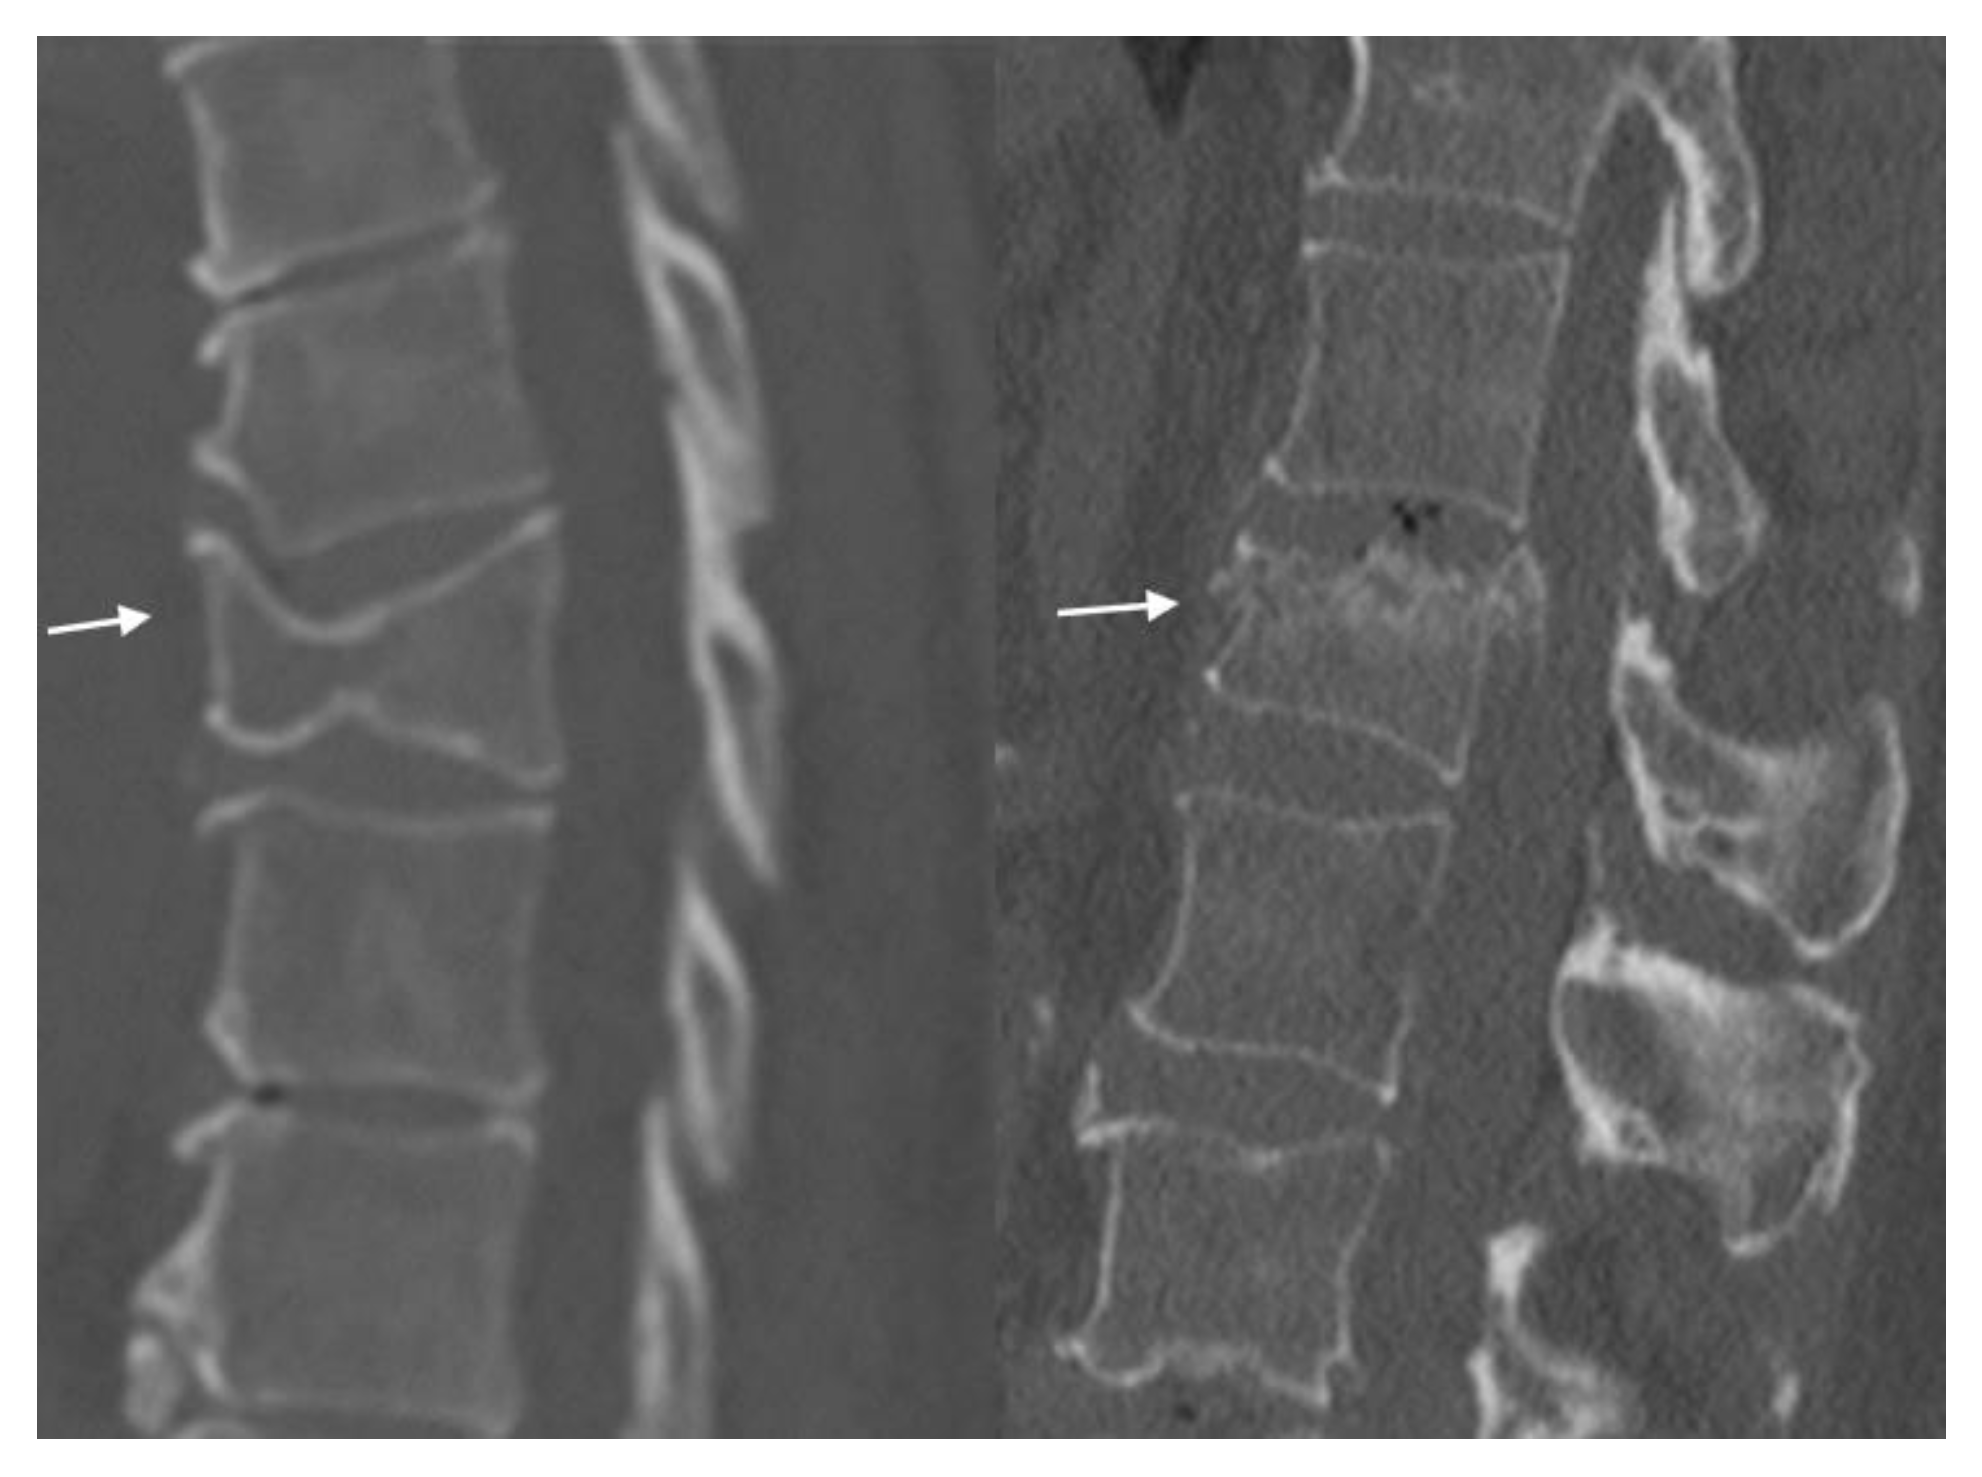

4.2. CT Scans